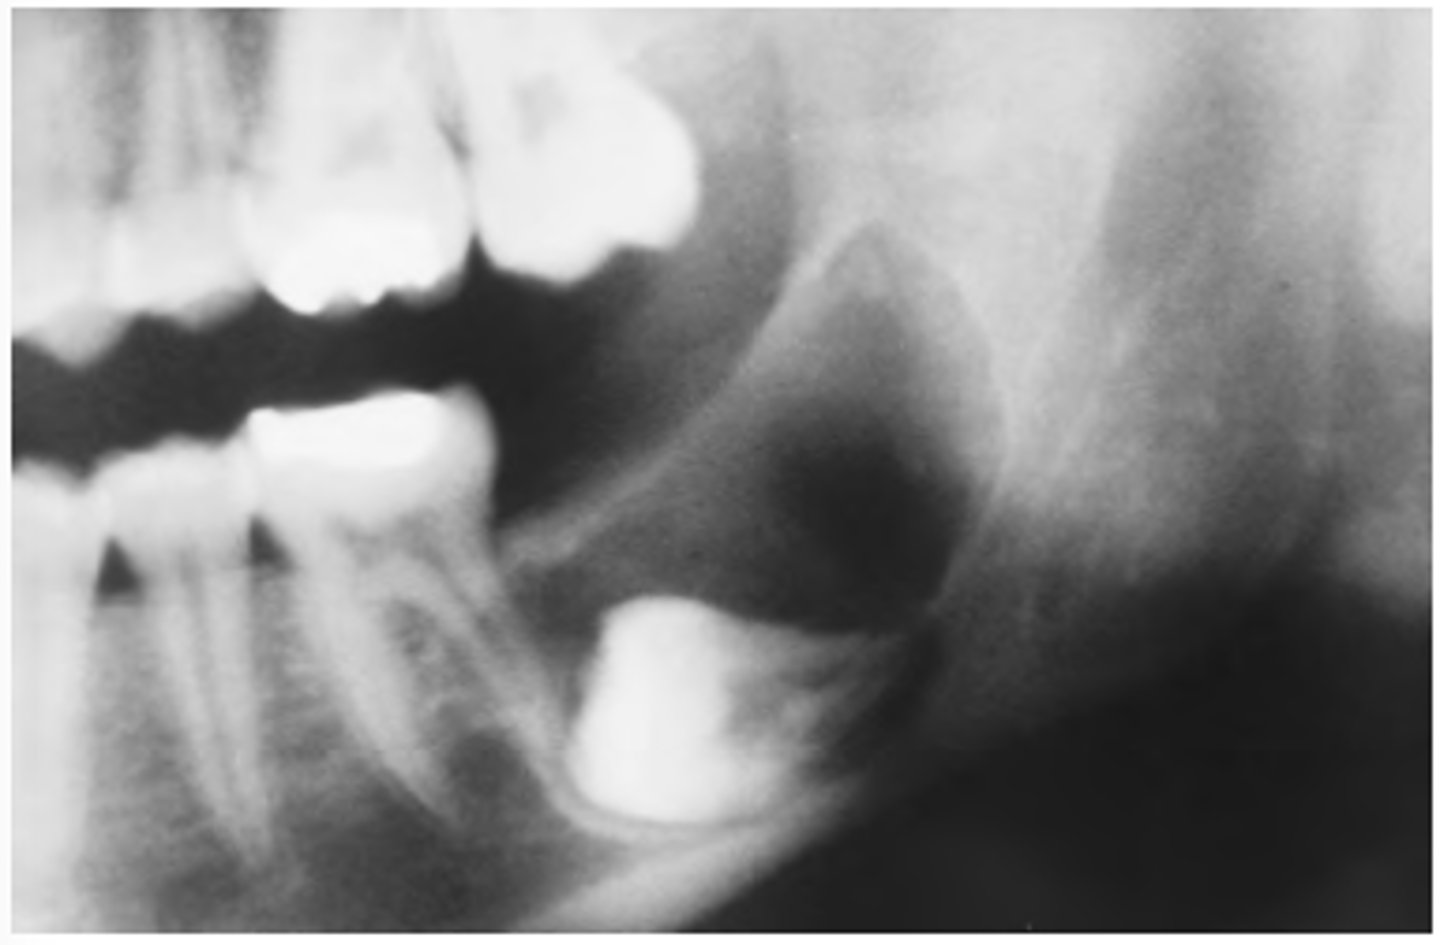

What are the radiographic features of ameloblastomas?

⢠unilocular radiolucency (early lesions)

⢠multilocular radiolucency (honeycomb/soap bubble) (large lesions)

⢠cortical thinning/bone expansion

⢠resorption of adjacent tooth roots + tooth displacement